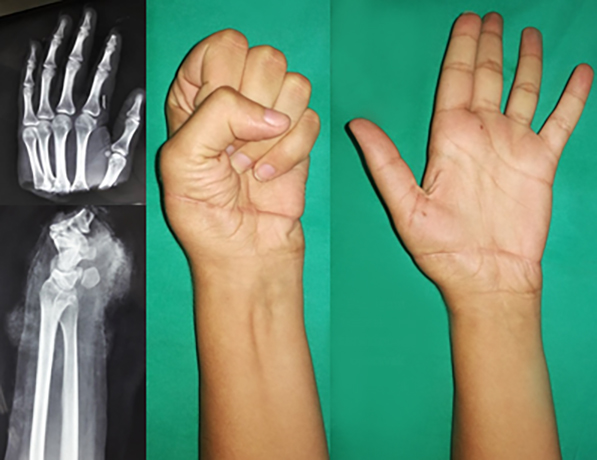

levo: Muškarac 52 godine replantacija palca 7 nedelja posle operacije.

desno: Replantacija šake – spoljašnja fixacija kosti ProFix aparat |